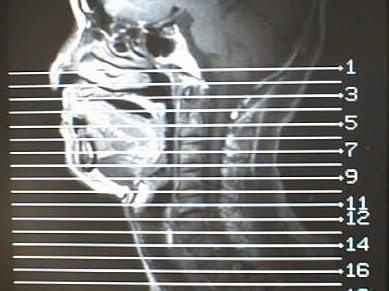

MRI画像比較

中咽頭末期がんMRI画像③

入院当時MRI画像③

中咽頭末期がん消滅時MRI画像③

入院3か月後癌消滅MRI画像③